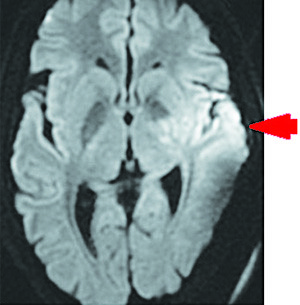

Рисунок 7.Сливные очаги гиперинтенсивного сигнала в области скорлупы, внутренней капсулы, в головке хвостатого ядра и паравентрикулярном белом веществе головного мозга на DWI-режиме.Результаты проведения МРТ головного мозга на 10-е сутки госпитализации (см. рис. 7 и 8). В области скорлупы и внутренней капсулы, в головке хвостатого ядра и паравентрикулярном белом веществе определяются сливные очаги гиперинтенсивного сигнала на Т2FLAIR и DWI, с умеренным ограничением диффузии на ADC, в бороздах мозжечка слева отмечается гиперинтенсивный сигнал на Т2FLAIR. Срединные структуры не смещены. Желудочки мозга не расширены. Субарахноидальные пространства конвекса не изменены. Признаков нарушения ликвородинамики не выявлено.

Рисунок 8.Умеренное ограничение диффузии на ADC-режиме.Базальные цистерны без особенностей. Селлярная область и основание черепа не изменены. Полость турецкого седла не расширена. Гипофиз обычных размеров и формы, контуры ровные, структура однородная. Дифференцировка на нейро- и аденогипофиз сохранена. Мосто-мозжечковые углы свободны, внутренние слуховые проходы не расширены, симметричны.

Краниовертебральный переход без особенностей. Миндалины мозжечка расположены обычно. На бесконтрастной ангиографии значимых деформаций, окклюзий артерий виллизиева круга не выявлено. В зону сканирования попадает стентированная часть левой ВСА с сохранным кровотоком.